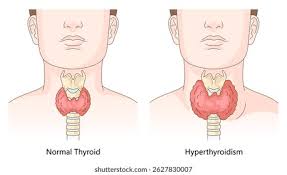

Thyroid Disorder

Ayurveda offers holistic treatments for thyroid disorders, aiming to restore hormonal balance, support thyroid function, and alleviate associated symptoms. Regular exercise, yoga, and pranayama can help improve metabolism and reduce stress levels. Ayurvedic therapies like Panchakarma may also be recommended to eliminate toxins and restore balance in the body.